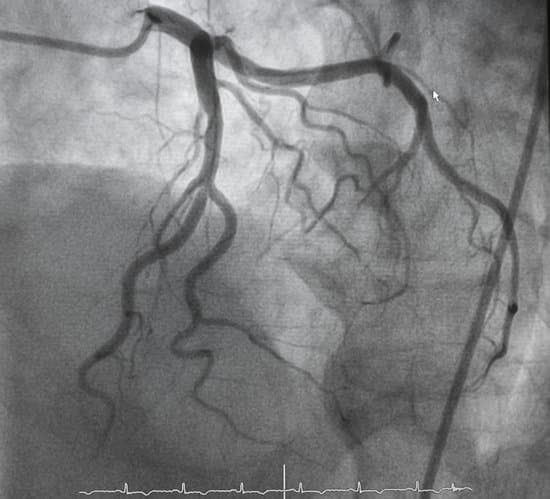

조영제 주입과 영상 촬영: 카테터를 통해 조영제(방사선 불투명 물질)를 관상동맥에 주입하고, X-레이 영상을 촬영하여 혈관의 이미지를 얻습니다.

관상동맥 조영술(Coronary Angiography)은 심장의 혈관 상태를 평가하기 위해 실시하는 진단 방법입니다.

이 절차는 관상동맥의 협착이나 폐색을 확인하여 심장 질환의 진단, 치료 계획 수립, 그리고 예후 판단에 중요한 정보를 제공합니다.